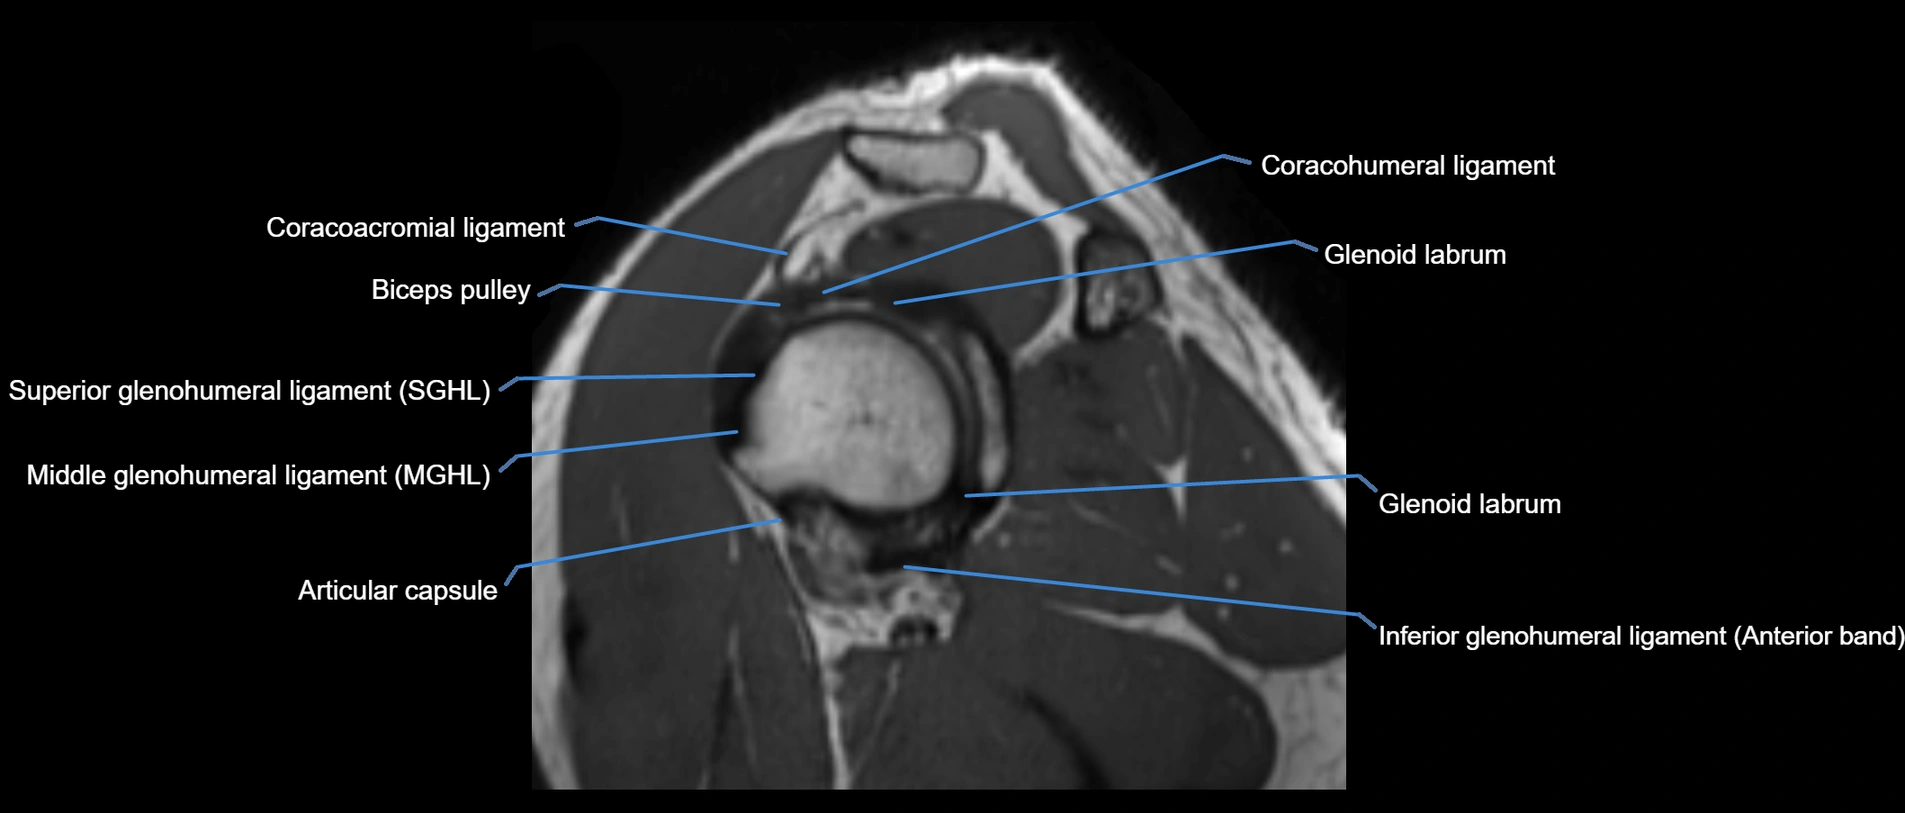

MRI Appearance

• T1-weighted images:

• Normal ligament: Low signal (dark linear band) spanning acromion to clavicle.

• Surrounding fat planes: Bright, delineating the ligament clearly.

• Marrow of clavicle and acromion: Bright due to fatty content.

• Tears: Discontinuity or irregular thickening with intermediate-to-bright signal.

• Chronic injury: Thinning, fraying, or irregular low-signal fibers with adjacent scarring.

• T2-weighted images:

• Normal ligament: Low signal, homogeneous.

• Partial tear or sprain: Focal hyperintensity or thickening.

• Complete tear: Discontinuity with fluid-bright gap between clavicle and acromion.

• Associated edema: Bright signal in distal clavicle or acromion marrow.

• STIR:

• Normal ligament: Dark linear band.

• Injury or inflammation: Bright hyperintense signal in and around ligament fibers.

• Highlights periligamentous soft-tissue edema, especially in acute trauma.

• Proton Density Fat-Saturated (PD FS):

• Normal ligament: Low signal, uniform thickness.

• Partial tear or sprain: Bright signal or contour irregularity.

• Complete tear: Clear discontinuity with bright signal gap and joint effusion.

• Excellent for assessing joint capsule, coracoclavicular ligaments, and periarticular edema.

MRI images

image